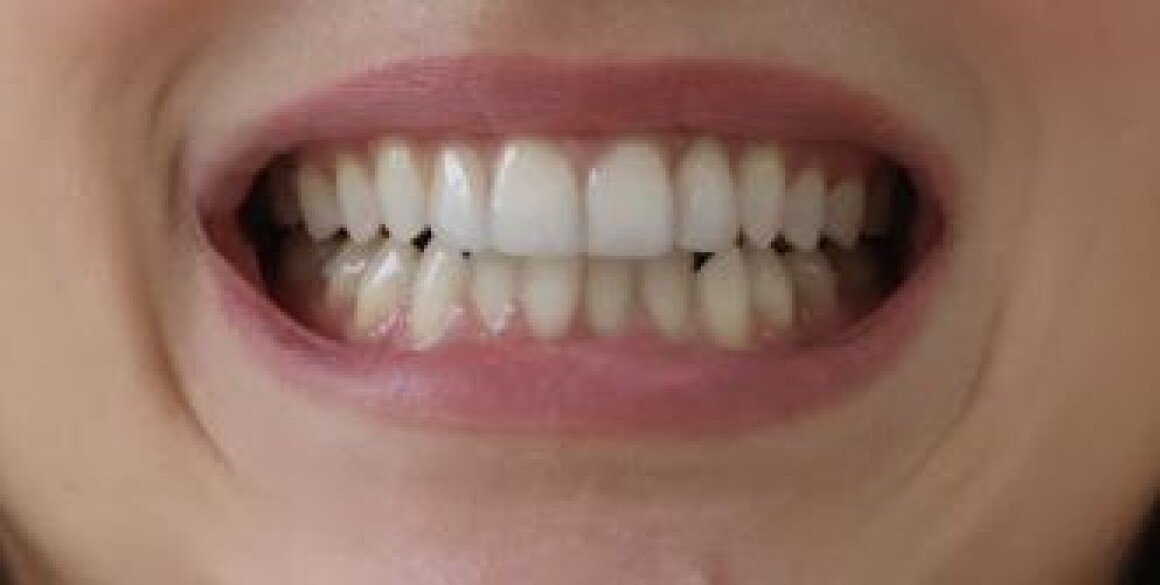

Виниры

Проблема : скол зуба, эстетика